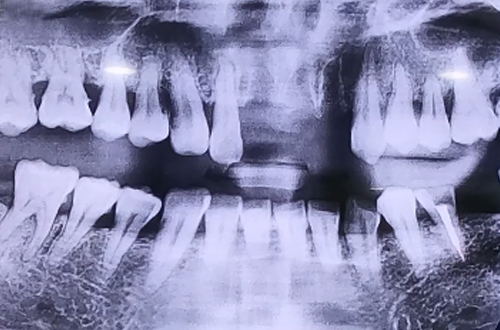

앞니 치아가 여러 개 빠진 상태의 임플란트 사례

넘어지면서 앞니 치아가 여러 개 빠진 환자분이십니다.

첫번 째 앞니와 두 번째 앞니, 오른쪽 앞니가 빠진 상태로 방문하셨는데

오른쪽 두 번째 치아의 경우에도 많이 흔들리고 주변의 잇몸뼈들이

으스러져 있는 상태였기 때문에 두 번째 앞니까지 발치한 뒤

임플란트 2개로 치아 4개를 동시에 만들어 주는 치료를 계획하여 진행해드렸습니다.

당일 즉시 임플란트 수술을 진행하면서 뼈이식을 통해 단단하게 보강해 준 뒤

즉시 식립을 진행하고 임시치아를 만들어드리며 치료를 마무리하였습니다.